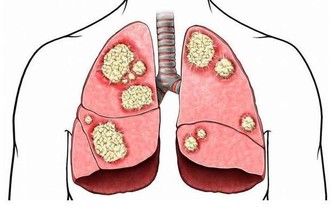

關節炎是一種影響所有年齡段人群的常見病症,它的症狀包括運動受限制、關節疼痛、關節出現炎症,以及受影響區域的皮膚紅腫發燙。